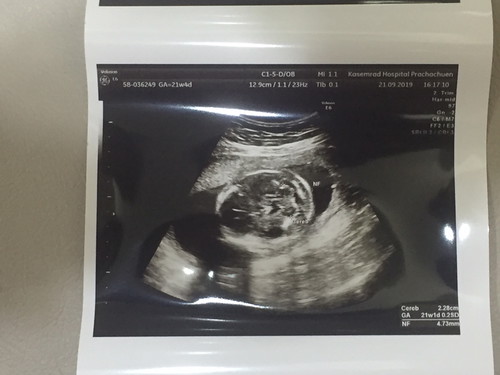

ตรวจดูความสมบูรณ์ครับ หมอบอกว่าสมบูรณ์ดีทุกอย่าง อยู่ในเกณฑ์ ไม่มีอะไรผิดปกติครับ และเป็นผู้ชายแน่นอนครับ